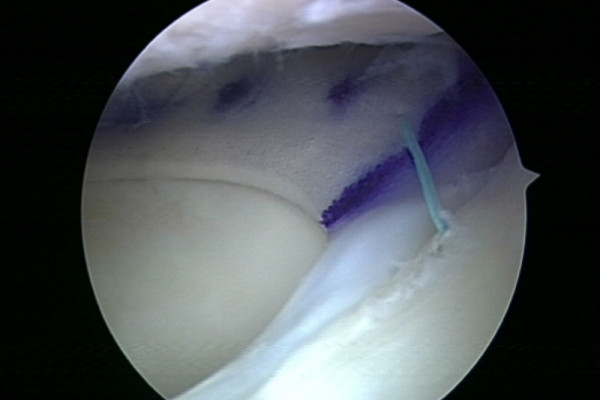

Kann der Meniskus trotz aller Bemühungen nach einer Verletzung nicht erhalten werden oder wurde er im Rahmen einer früheren Operation zu großen Teilen entfernt, besteht die Möglichkeit den fehlenden Anteil durch ein Meniskusimplantat (CMI) zu ersetzen. Dieses Implantat besteht aus Kollagen, dem Hauptbestandteil des natürlichen Meniskus. Das Implantat wird auf die Größe des Defektes zugeschnitten und im Rahmen einer Gelenkspiegelung in den Defekt eingebracht. Die Fixierung erfolgt mittels Nähten analog zu einer klassischen Meniskusnaht.

Im Lauf der Zeit wird das Implantat von körpereigenen Stammzellen bevölkert und von einer Narbenplatte überwuchert. Hierdurch kann die Funktion des Meniskus, zumindest zum Teil wiederhergestellt werden.

Meniskusimplantat

Meniskusimplantat nach Implantation ins Kniegelenk